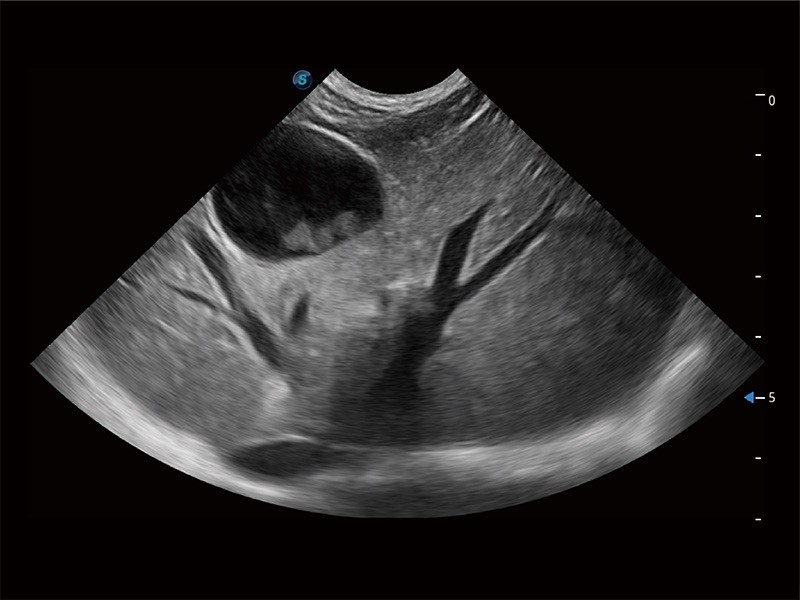

Introduction to the abdomen

This course is applicable to recent graduates, nurses or anyone inexperienced in sonography wishing to learn how to perform an abdominal ultrasound scan. From understanding the buttons on your machine, to learning your way around the abdomen, we can help your team to become proficient in abdominal ultrasound.

- Liver and Gallbladder

- Spleen

- Gastrointestinal tract

- Kidneys

- Urinary bladder